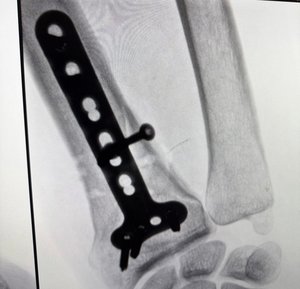

Зокрема, за рік медики виконали понад 200 ендопротезувань колінних і кульшових суглобів, більше 50 трепанацій черепа — у випадках злоякісних інсультів та черепно-мозкових травм та понад 600 операцій при переломах із застосуванням БІОС та МОС.

Окрім цього, щодня медики надавали ургентну та планову допомогу пацієнтам із різною патологією опорно-рухового апарату. Йдеться про ортопедичні операції різної складності — коригуючі остеотомії, вертебропластики, втручання на м’яких тканинах.